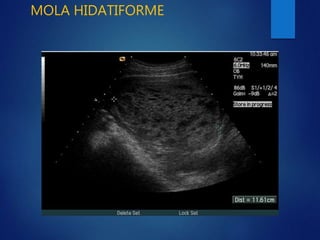

MOLA HIDATIFORME

• O tambien denominada mixoma

placentario.

• Es una degeneracion quistica edematosa de

las vellosidades coriales.

• Puede abarcar la placenta y el resto del

complejo ovular.

• No se conoce aun la etiopatogenia del

SIGNOS ECOGRAFICOS

• La ecografia posibilita un diagnostico de certeza

casi en la totalidad de los casos.

• La cavidad uterina se encuentra llena de multiples

ecos que dan una imagen caracteristica

tradicionalmente denominada

• Signos ecograficos..

Tormenta de nieve o panal de abejas.